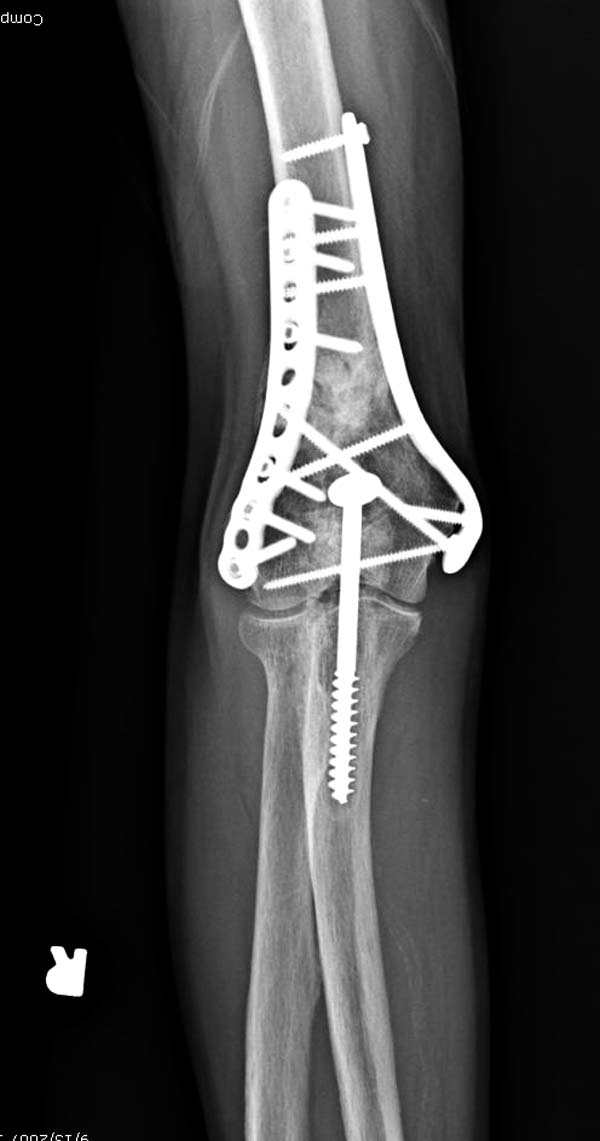

Если удастся репонировать закрыто сустав, тогда доступ к задней поверхности плеча можно достичь с двух сторон трицепса: медиального и латерального. Для фиксации можно применить 90 градусные пластины или Acumed key stone концепт с двух сторон.

Здесь открытый перелом, временный наружный фиксатор и окончательная фиксация пластинами. Второй случай фиксация без остеотомии отростка пластинами Biomet-DePuy...